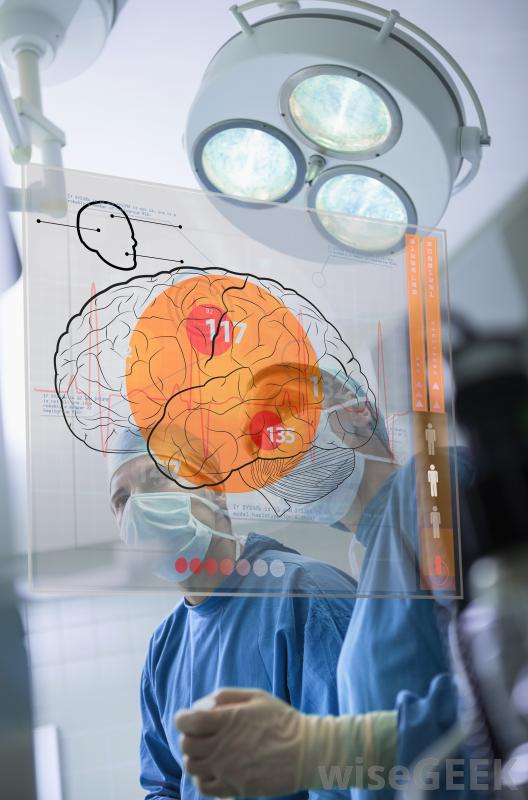

脑瘤可能导致患者思维模糊和思维混乱外科手术是治疗多种癌症的首选治疗方法之一,尤其是与药物或放射治疗结合使用时,外科手术通常能极大地改善病人的预后,发生在脑部的肿瘤往往更难用手术来治疗,因为大脑的功能既脆弱又重要MRIs和其他脑成像技术可以用来定位和测量肿瘤。恶性肿瘤可以在大脑的许多不同区域及其支持结构中形成大脑的外围区域,例如靠近神经的区域,将感觉输入输入大脑,更容易成为外科治疗的好选择生长在负责基本运动功能的大脑区域或位于大脑结构深处的肿瘤不太适合手术用化疗缩小不能手术的脑瘤。在某些情况下,即使是扩散很慢的肿瘤,如果它形成于大脑中特别敏感或关键的部位,也可能被归类为恶性肿瘤位于大脑这一部分的肿瘤很可能是一种无法手术治疗的脑癌。然而,尽管无法通过手术治疗,但并非所有这些癌症都会立即危及生命。

手术可以是一种有效的脑癌治疗方法,特别是与药物和放射治疗。